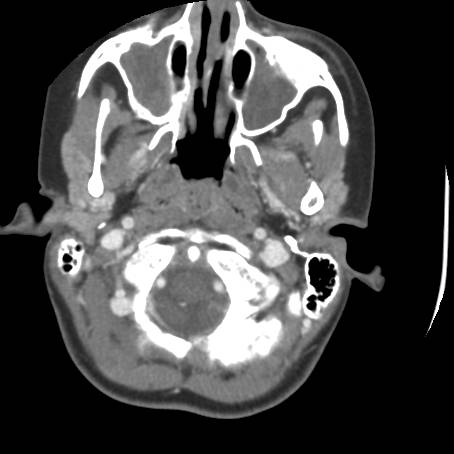

![]() Figure 5a |

Describe CT.